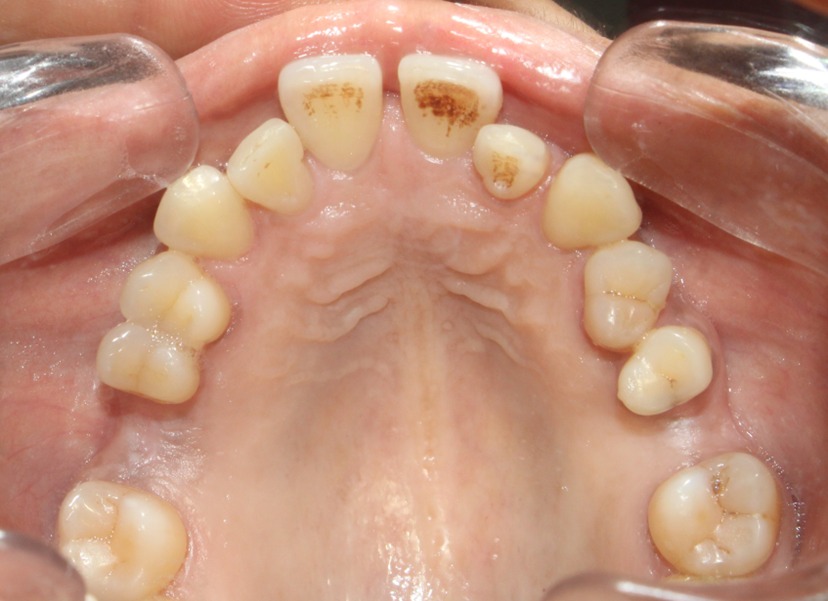

Before & After Results

At Aline Dent, we take pride in delivering visible and lasting improvements in our patients’ smiles. Our before-and-after results highlight the effectiveness of modern dental treatments combined with personalized care. This gallery showcases real dental cases treated at our clinic, giving you a clear idea of how different dental concerns can be corrected with the right treatment approach.

From minor corrections to complete smile enhancements, these teeth transformation results demonstrate how professional dental care can improve both oral health and appearance. Our experienced dental team carefully evaluates each patient’s needs and creates customized treatment plans to achieve natural, healthy, and confident smiles.

In this gallery, you will find a variety of smile makeover cases, including treatments for crooked teeth, gaps, discoloration, damaged teeth, and other common dental concerns.